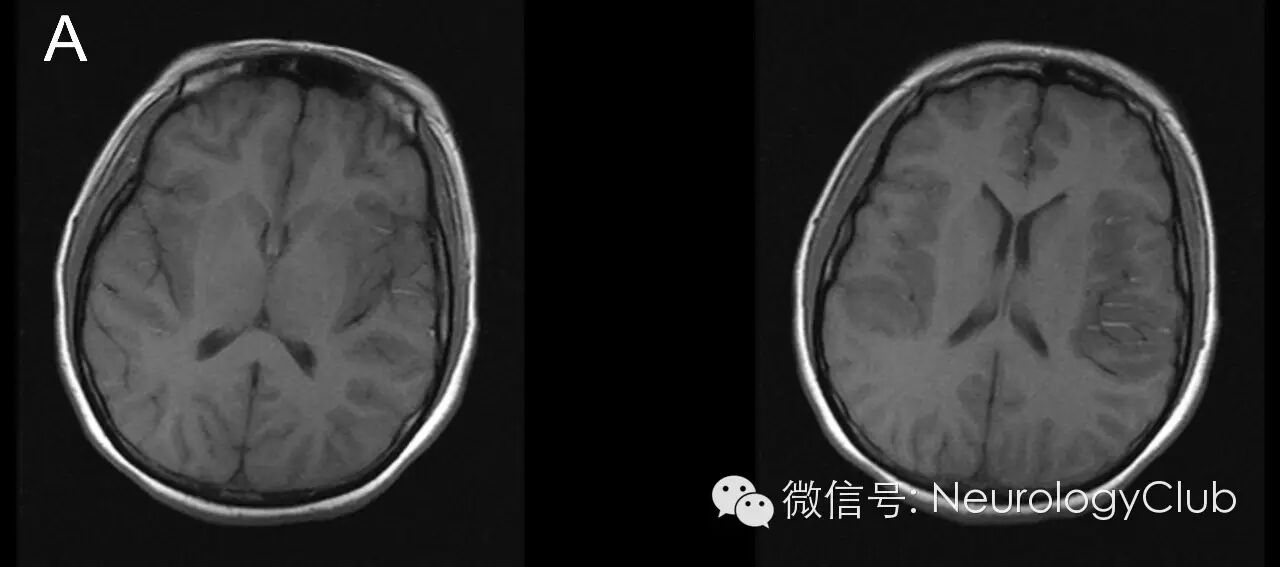

病变侵犯大脑额、颞叶、枕叶及岛叶皮质区,呈T1WI低信号,T2WI/FLAIR高信号,未累及基底节。病变区与豆状核之间边界清楚,凸面向外,如刀切样,称“刀切征”。常见于病毒性脑炎,特别是单纯疱疹病毒性脑炎。罕见于鸟氨酸氨甲酰基转移酶缺乏症等。

患者,女,31岁,主诉“发热伴头痛5天,肢体抽搐1天”

(图1:T1WI)

(图2:T2WI)

在各种病毒所致脑炎中,单纯疱疹病毒性脑炎的影像学最具特征性,可归纳为:①病变多先累及单侧或双侧颞叶,部分病例可向额叶或枕叶发展,单独发生于额叶、枕叶及顶叶者少见;②病变均与豆状核之间界线清楚,凸面向外,如刀切样,称刀切征,许多学者认为这是本病最具特征性的表现;③CT平扫呈片状不规则低密度,,MRI检查呈长T1、T2片状高信号,以T2WI上病变显示最为清楚;④不增强或线样脑回状增强。主要位于病变的边缘部分。增强与否可能与病变的严重程度有关,因为广泛的血管炎和脑组织灶性坏死是出血强化的病理基础;⑤严重者可有占位效应。